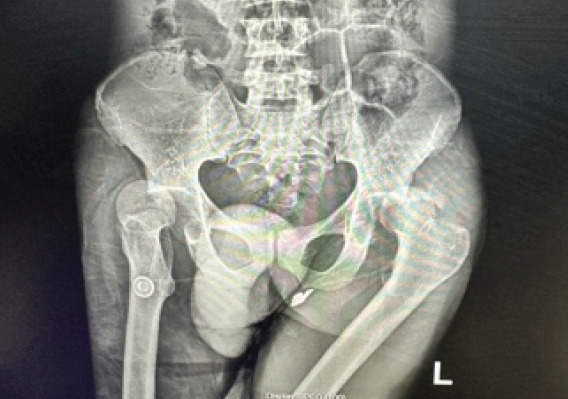

Introduction: Asymmetrical hip dislocations are rare injuries. The native hip joint is inherently stable, so both joints will dislocate in a high-energy setting. Therefore, it is imperative to exclude other associated injuries and fractures and ensure both hips are reduced timeously.

Case report: We present a rare case of a 46-year-old male patient who presented with asymmetrical complex hip dislocations following a pedestrian-vehicle accident. Both hips were reduced; however, the left acetabulum posterior wall needed open reduction and internal fixation.